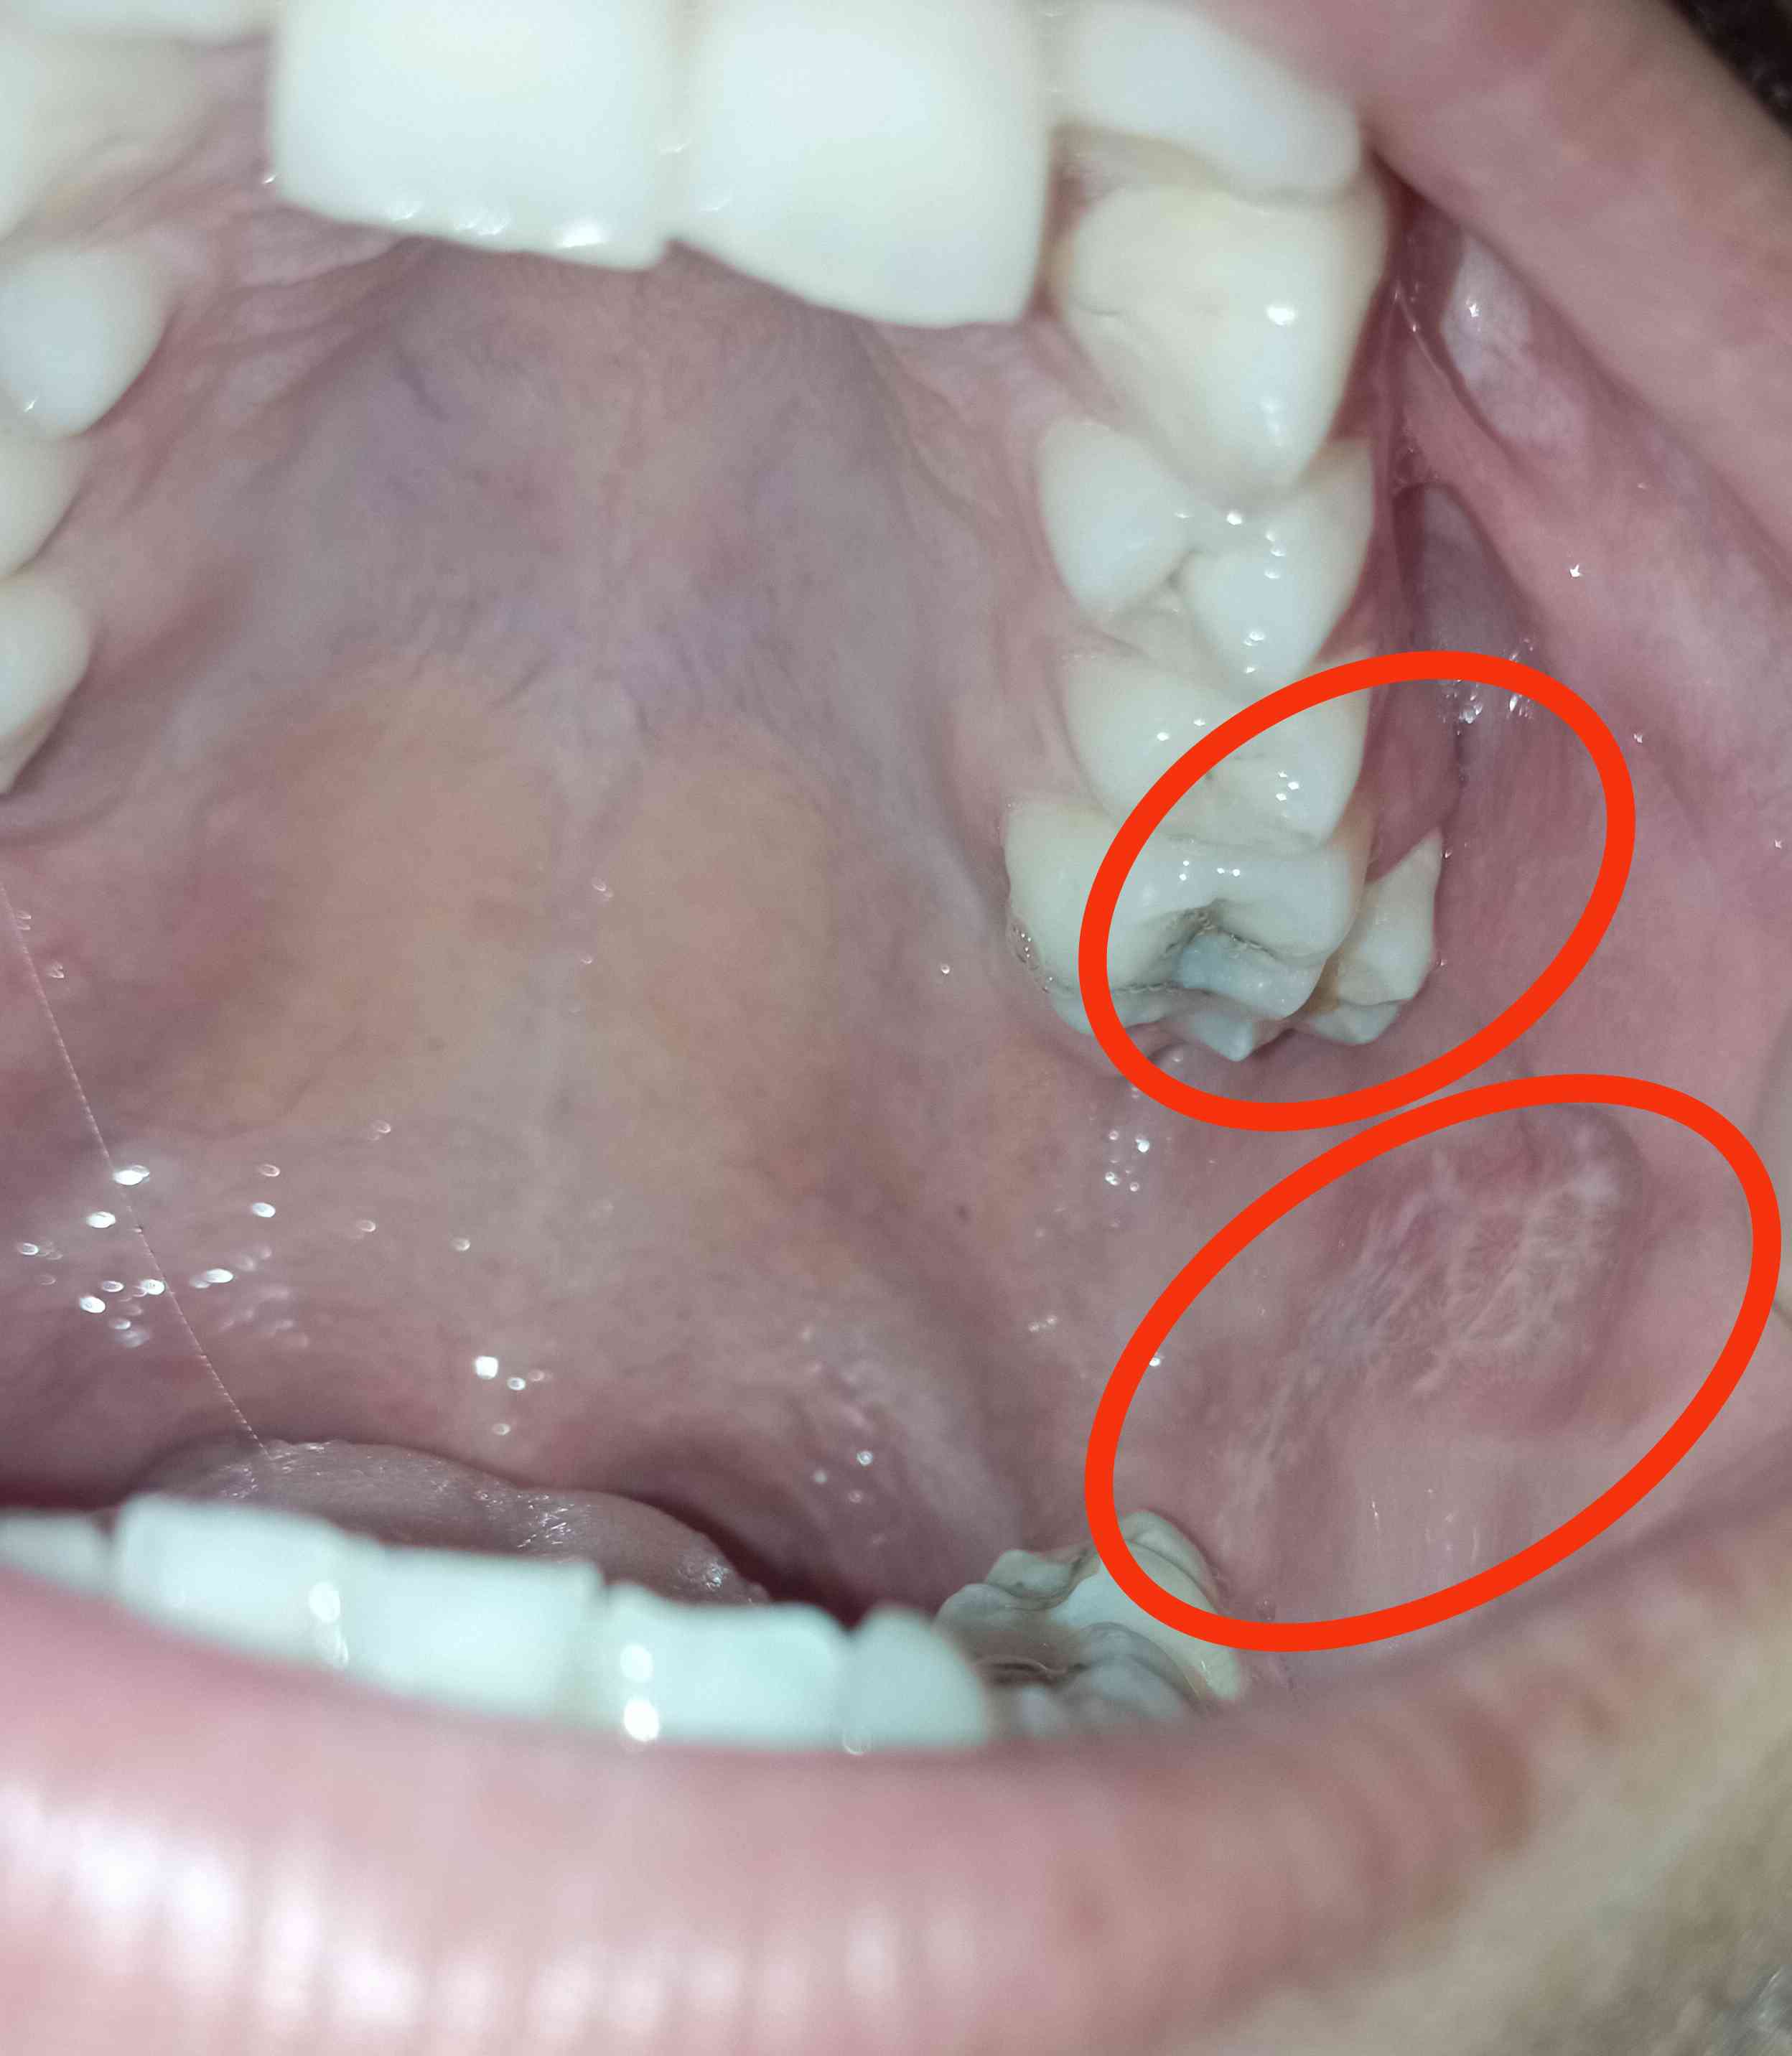

بعد نمو ضرس العقل تحرك الضرس المجاور عن مكانه (كما في الصورة). أزلت ضرس العقل ظنًّا أن الضرس ستعود لمكانها، لكنها ما زالت مائلة ويظهر بياض عند الاحتكاك دون ألم واضح .

السلام عليكم سلامات واضح من الصورة عندك مشكلة في ترتيب ورص الأسنان تحتاج إلى تقويم يجب الذهاب الى اخصائي تقويم مع ايقاف بعض العادات مثل العض على الاسنان او الاكل بجانب واحد نسأل الله أن يكتب عاجل الشفاء واتمنى تكون الاجابة واضحة 1 2025-10-27T17:25:08+00:00 2025-10-27T17:25:08+00:00